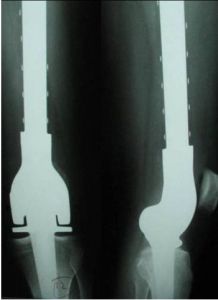

(1)廣泛切除:適應於I級惡性纖維組織細胞瘤;術前輔助治療反應滿意的II期腫瘤,也可行廣泛切除。骨內惡性纖維組織細胞瘤切除後根據部位可選擇適當的重建方法:如關節融合術、人工假體置換術、同種異體骨關節移植術、異體骨和人工假體複合移植術、帶血管自體骨移植術、瘤骨滅活再植術等。

患者,男,56歲,左脛骨BMFH定製假體置換術後正側位X線片(略)

手術方式的選擇:由於大多數的BMFH為高度惡性腫瘤,腫瘤分期為ⅡA和ⅡB期,保肢手術適用於ⅡA期和對化療敏感的ⅡB期腫瘤,病灶周圍大的神經血管未受累,可在安全邊界完整切除且通過重建可以獲得較好的功能。本組病例19例ⅡA期,19例ⅡB期皆進行了保肢術。保肢術中由於早期假體設計本身存在的局限性,套用較少,主要以腫瘤切除瘤骨骨殼滅活再植術、腫瘤切除自體骨移植或異體骨移植術為主。由於術後併發症主要集中在瘤段骨滅活回植術後,包括復發、骨不癒合等,但近些年隨著假體設計技術及理念的提高,套用範圍大大擴大,逐漸成為保肢術的主流。本組病例主要採用腫瘤切除加定製假體置換和腫瘤切除瘤骨骨殼滅活再植術,腫瘤切除自體骨移植或異體骨移植術採用較少,可能與植骨的來源、腫瘤累及的部位及病例數較少有關。(2)輔助放療和化療。